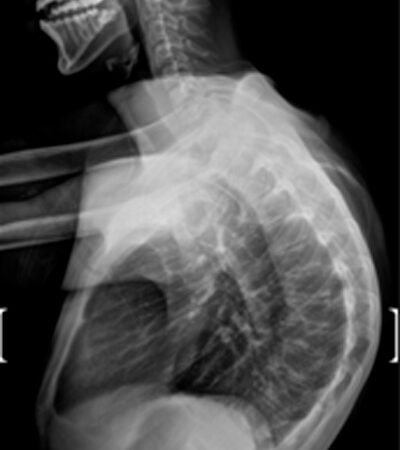

DIAGNOSI:

IPERCIFOSI DORSALE GRAVE

Radiografia dorsale pre operatoria

Intervento chirurgico eseguito:

STABILIZZAZIONE DORSO – LOMBARE CON OSTEOTOMIE CORRETTIVE

Radiografia dorsale post-operatoria